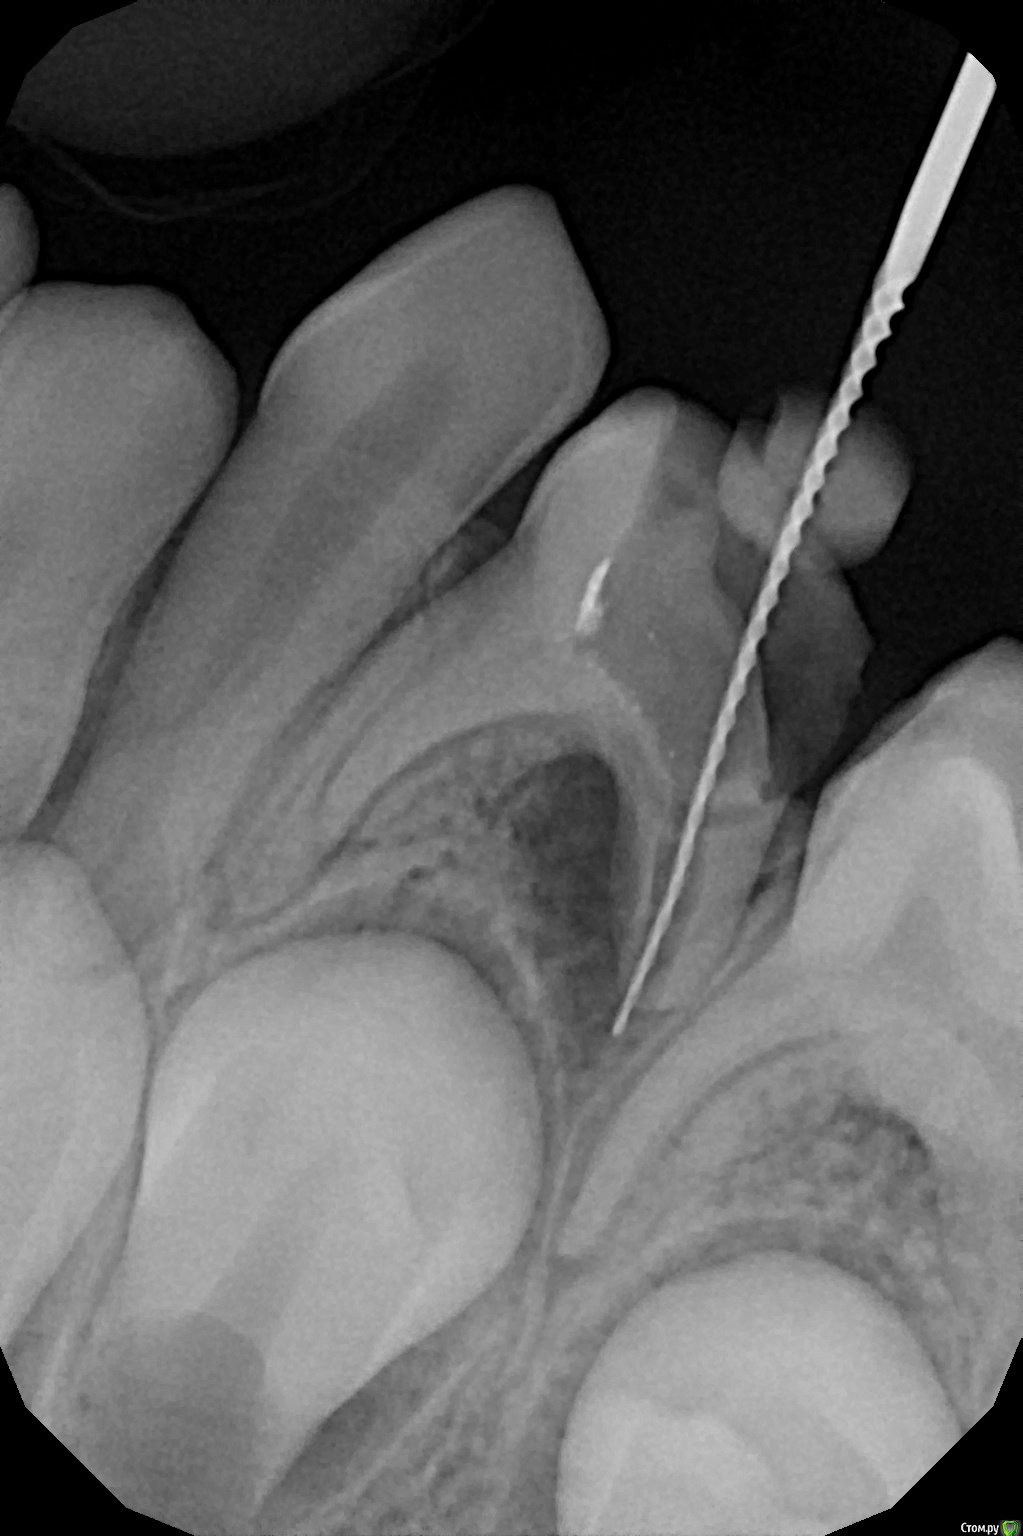

crown Опубликовано 9 декабря, 2016 Поделиться Опубликовано 9 декабря, 2016 О народ подтянулся, заодно и мой тогда посмотрите. 7 лет, 7.4, ранее резорциненный, в медиальных там все глухо, ток бором сверлить, в дистальном кальций оставил. Ссылка на комментарий

Джима Опубликовано 9 декабря, 2016 Поделиться Опубликовано 9 декабря, 2016 заживёт, постоит ещё немного. только метапекс из канала рассосётся очень быстро. Ссылка на комментарий

crown Опубликовано 9 декабря, 2016 Поделиться Опубликовано 9 декабря, 2016 заживёт, постоит ещё немного. только метапекс из канала рассосётся очень быстро.А если эодентом закатать? Ссылка на комментарий

Джима Опубликовано 10 декабря, 2016 Поделиться Опубликовано 10 декабря, 2016 быстротвердеющим низзя, обычным можно Ссылка на комментарий

crown Опубликовано 17 февраля, 2017 Поделиться Опубликовано 17 февраля, 2017 Кажись заживает, 2,5 месяца. Ссылка на комментарий

Brigita Опубликовано 17 февраля, 2017 Поделиться Опубликовано 17 февраля, 2017 Красавчики.И док и зуб))) 2 Ссылка на комментарий

Воркутов Опубликовано 13 мая, 2017 Поделиться Опубликовано 13 мая, 2017 Молодцы!!! Зуб спасен , ребенок доволен!! Ссылка на комментарий